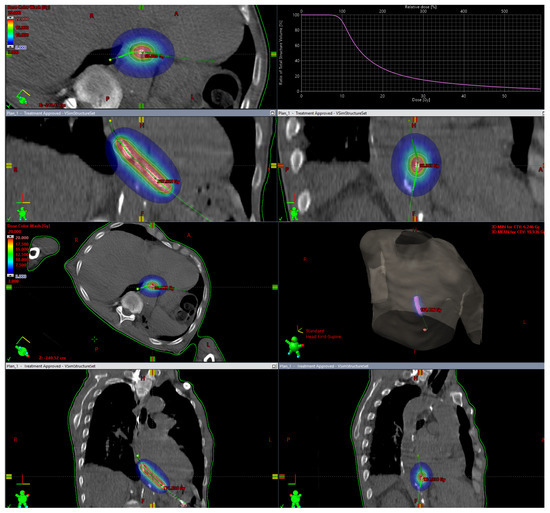

3. Brachytherapy Combined with Teleradiotherapy in Advanced, Non-Operative Stages

4. Brachytherapy in the Palliative Treatment of Esophageal Cancer

- Omari, J.; Heinze, C.; Wilck, A.; Hass, P.; Seidensticker, M.; Damm, R.; Fischbach, K.; Ricke, J.; Pech, M.; Powerski, M. Image-guided interstitial high-dose-rate brachytherapy in the treatment of metastatic esophageal squamous cell carcinoma. J. Contemp. Brachytherapy 2018, 10, 439–445. [Google Scholar] [CrossRef]